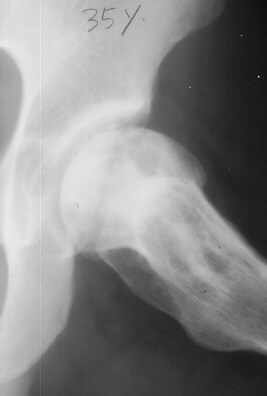

At 28 years of age, he had been having increasing pain in his right hip. He had a limp when he was tired. Positive Trendelenburg's sign was observed on the right. Internal rotation was limited to 25 degrees. All other motions were normal. X-ray showed cystic change. At the 29 years of age, he underwent bone graft of the right femoral head for degenerative cyst. At 35 years of age, only internal rotation was limited to 20 degrees. He still had pain in his hip that relates primarily to weather or to excessive walking. Only internal rotation was limited to 20 degrees. He had hip pain at the extremes of flexion and internal rotation. X-ray showed the progression of the cystic change. CT which was performed because of the question of loose bodies in the hip did not seem likely that the densities were actually in the hip joint. The antero-medial location of the cysts facing the anterior margin of the acetabulum was well depicted in CT.

28 yrs, 29 yrs, 30 yrs, 35 yrs .